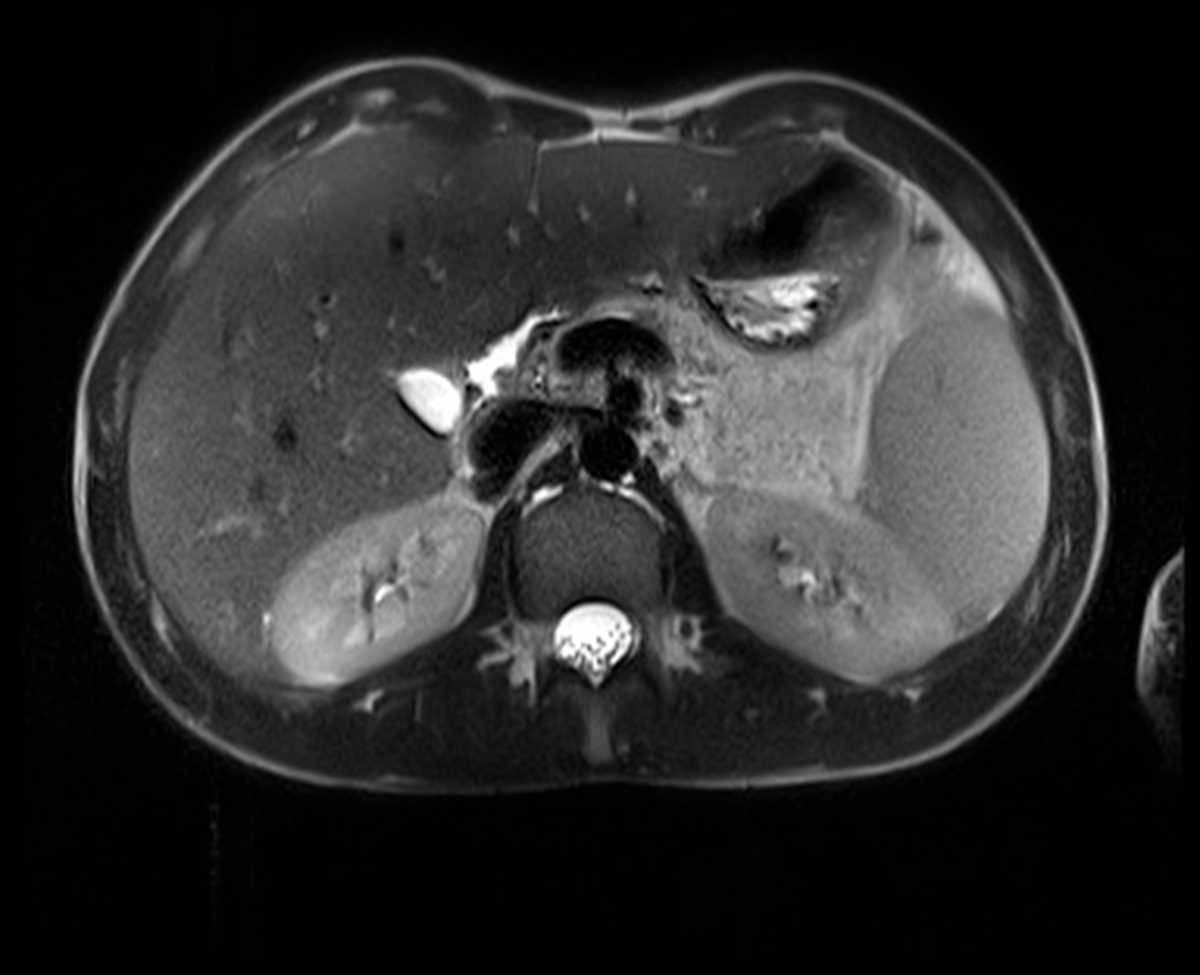

Focal nodular hyperplasia (FNH)

Multiple CT and MR images demonstrate homogeneous, round, markedly hypervascular mass in the right posterior liver lobe which is relatively isointense on the venous and delayed phase images, compatible with FNH